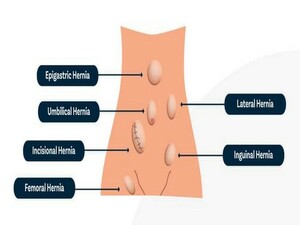

His special interests are in the field of Laparoscopic Hernia Surgery, Laparoscopic Upper G.I Surgery, Laparoscopy in Gastrointestinal Cancers and Bariatric Surgery. He is also actively involved in publications in peer – reviewed journals.